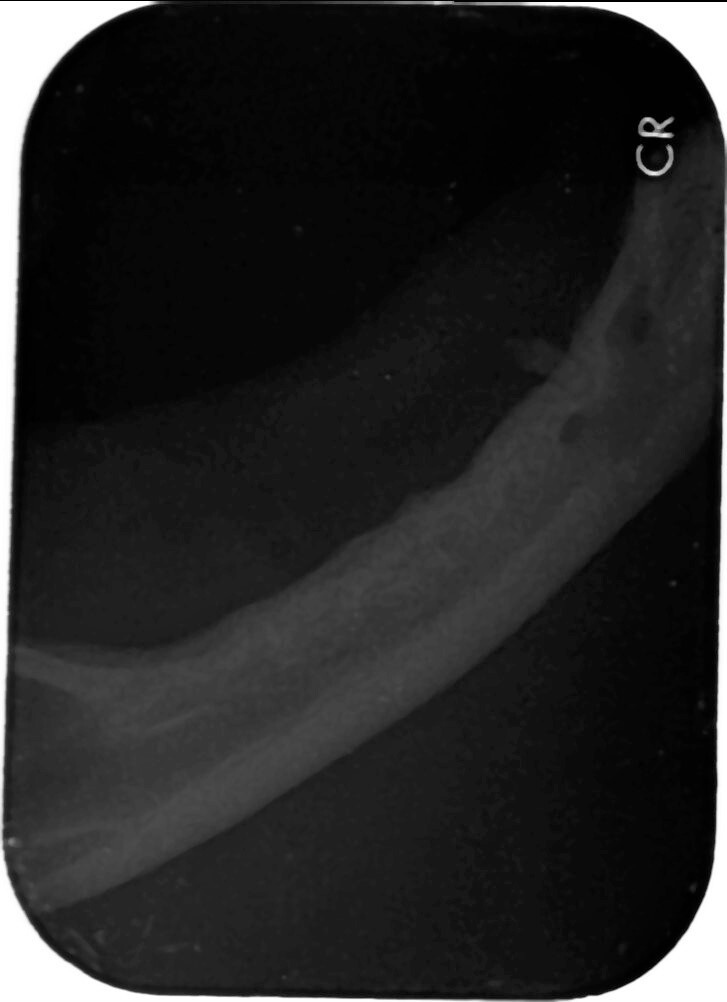

於他家醫院建議拍攝齒科x光 懷疑齒根殘存

10/5門診時 口內檢查可摸到雙側下顎有殘存齒根

10/18維康麻醉進行齒科x光

及殘存齒根拔除

只發現下顎雙側各一齒根(如同門診可觸摸處)

本筆醫藥費用即為盈盈於維康進行齒科X光及殘存齒根拔除的費用